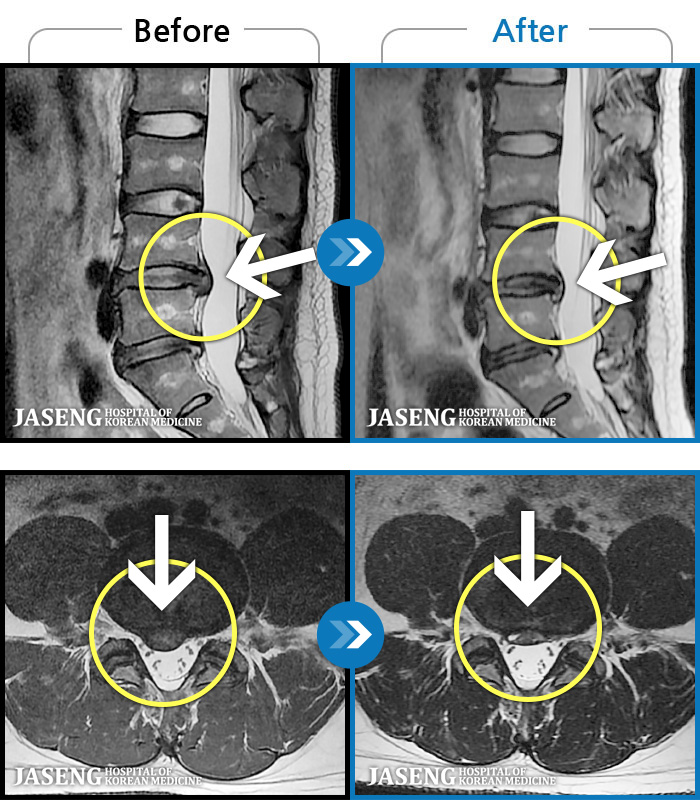

66 MRI ũ ʸ Ȯϼ.